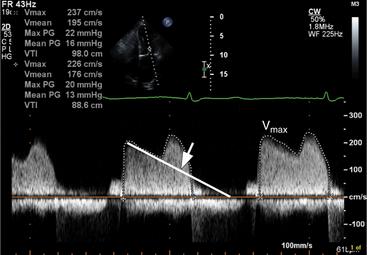

Mitral Gradient By CW Doppler In Mitral Stenosis – All About

Mitral gradient by CW Doppler in mitral stenosis – All About johnsonfrancis.org

mitral gradient stenosis doppler

mitral pressure gradient doppler mv cw stenosis valve echocardiography valvular measured disease wave heart

Mitral functional stenosis. Mitral pressure gradient doppler mv cw stenosis valve echocardiography valvular measured disease wave heart. Mitral stenosis prolapse regurgitation valve